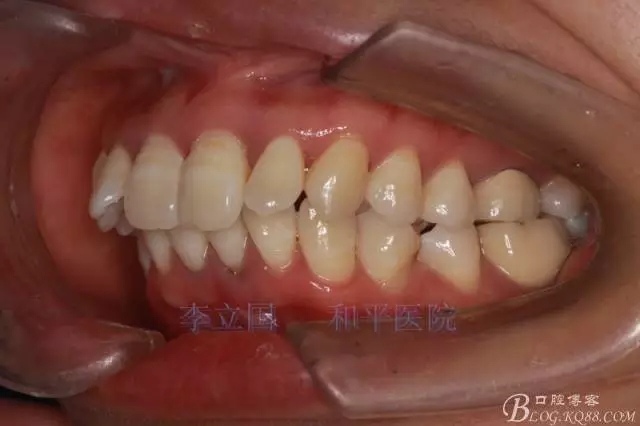

”嘴凸牙不凸”病例治療要點(diǎn)

1.患者上前牙直立,面型前突,典型的嘴凸牙不吐,關(guān)鍵是前牙轉(zhuǎn)矩控制,建議使用高轉(zhuǎn)矩托槽。

2.磨牙關(guān)系一側(cè)完全遠(yuǎn)中,一側(cè)遠(yuǎn)中尖対尖,采用兩個(gè)上4,一個(gè)下1的拔牙模式。

4.使用長(zhǎng)牽引鉤,使?fàn)恳咏项M骨阻抗中心,防止上頜骨的順時(shí)針旋轉(zhuǎn)。